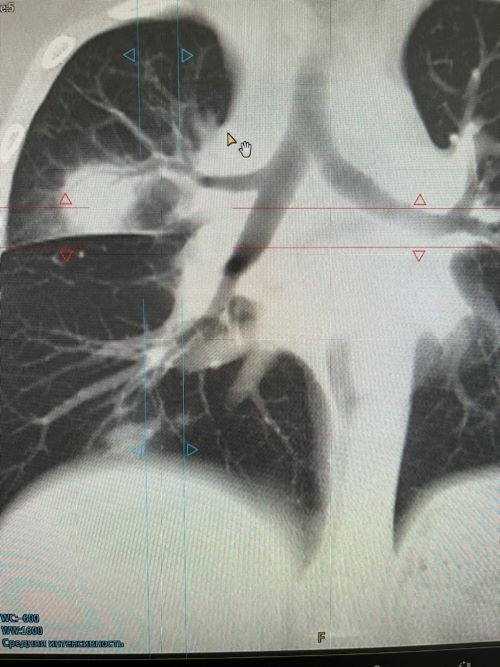

После проведённого сканирования были выявлены поражения в обоих лёгких, с выраженным инфильтратом в верхней доли правого лёгкого.

После интерпретации полученных снимков пациентке выставлен диагноз: Двустроронняя полисегментарная пневмония. Лимфоаденопатия ВГЛУ. Образование ? в верхней доле правого лёгкого.

По окончании лечения рекомендовано контрольное обследование на МСКТ для исключения новообразования.